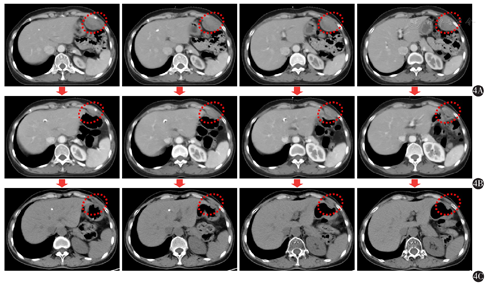

2016年6月15日查胸部CT示:胸腺瘤术后、放疗后,左肺结节影,左侧胸膜局部增厚。2016年8月8日复查胸部CT示:左肺结节影较前增大,考虑转移。2016年8月16日于当地医院行左肺病灶伽玛刀治疗。2016年9月20日查胸部CT示:左肺结节较2016年8月8日片明显缩小。2016年9月22日至2017年2月4日予以DP方案(多西他赛120 mg第1天+奈达铂30 mg第1-4天)化疗6个周期,期间定期复查左肺病灶稳定。2017年12月5日查胸部CT示:左上腹、近肝左叶左侧腹壁占位,大小约23.8 mm×8.5 mm。未予特殊重视。后定期复查,腹壁包块渐进增大,患者无特殊不适主诉。2019年10月6日查腹部彩超示:左上腹腹壁低回声实质性包块,大小约3.9 cm×4.0 cm×6.1 cm,界限可辨,血流丰富。胸部CT示:肝左叶旁左侧腹壁不规则软组织密度影,宽基底贴近腹壁,大小约5.6 cm×2.8 cm,增强后强化不均匀(图4A)。门诊以"左侧腹壁肿块待查"收入我科,入院诊断:①左侧腹壁肿块待查;②胸腺瘤(B2/B3混合型,Masaoka Ⅳ期,肺内);③重症肌无力(眼睑型)。

入院后于2019年10月11日行彩超引导下左上腹壁包块穿刺活检术。术后病理示:(左上腹腹壁)肿瘤细胞呈圆形,卵圆形。免疫组化:(左上腹腹壁)肿瘤细胞TDT(+),CD5(+),CKpan(+),Ki-67(+,约30%),p53(+,约10%),CD56(-),CgA(-),Syn(-),CD20(-)。结合HE切片及病史,考虑为胸腺瘤转移(图1B)。患者及家属拒绝手术治疗及化疗,于2019年10月23日起予以左上腹壁转移灶姑息放疗(图2),GTV为影像学所示左侧腹壁转移灶,PGTV为GTV外放0.5 cm。第1阶段:GTV 3.0 Gy/次,共16次;PGTV 2.0 Gy/次,共16次;二次定位提示腹壁转移灶较前明显退缩(图4B),予以缩野加量。第2阶段:PGTV-new:2.0 Gy/次,共10次。

放疗第1天开始予以重组人粒细胞-巨噬细胞集落刺激因子(recombinant human granulocytic-macrophage colony-stimulating factor,rhGM-CSF)(商品名:特尔立,厂家:厦门特宝生物工程股份有限公司),皮下注射200 μg,第1-14天。治疗期间每周监测血常规变化,如图3。放疗期间并无明显发热、皮疹、肌痛、骨痛等不良反应。放疗结束后每3个月复查1次,采用实体瘤治疗疗效评价标准1.1标准评价疗效为部分缓解。末次复查时间2020年9月24日,即放疗后10个月,腹壁转移灶仍稳定且并无新发病灶,部分缓解维持时间为10个月且仍在持续(图4)。